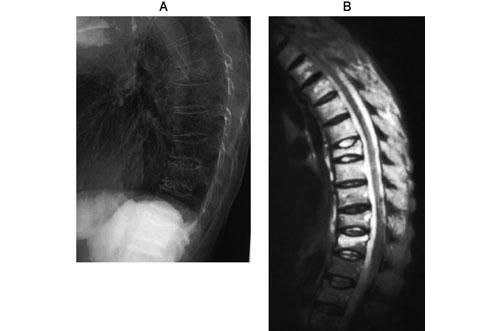

立位状態の患者に「後ろに反り返ってください」と指示したところ、図のような姿勢になり、これ以上に反り返ると転倒する危険があった。このときの評価で適切なのはどれか。